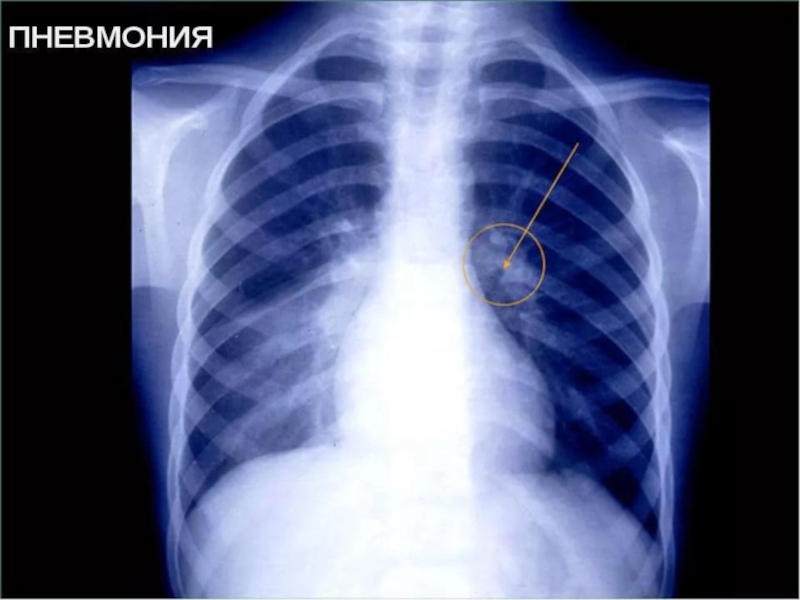

Слайд 60Очаговая бронхопневмония (уплотнение легочного рисунка в прикорневой зоне в нижней доле

правого легкого)